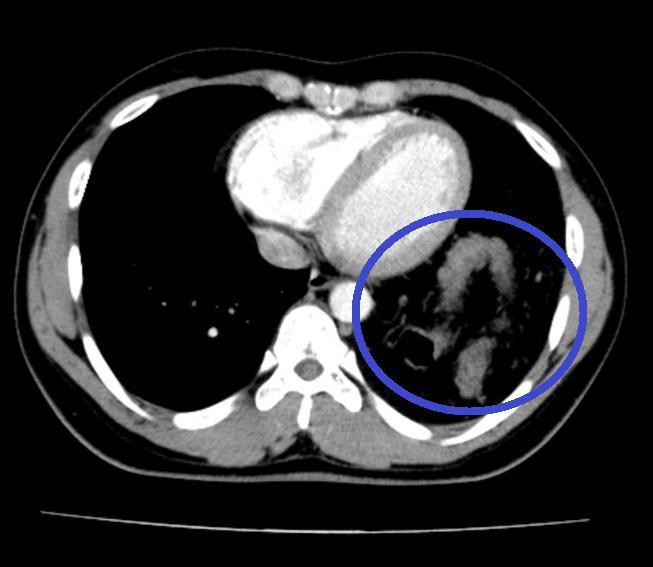

Tại đây, bệnh nhân đã được chỉ định chụp X-quang ngực và phát hiện có hình bóng hơi của ruột ở trên ngực trái. Bệnh nhân được hoàn thiện thêm các xét nghiệm cận lâm sàng và hội chẩn thêm các chuyên khoa, chụp cắt lớp khẳng định có thoát vị tạng bụng qua cơ hoành lên ngực trái.

| Hình ảnh chụp cắt lớp vi tính phát hiện đại tràng chui lên ngực trái bệnh nhân. Ảnh: BV. |

Bệnh nhân được chỉ định mổ nội soi để sửa tổn thương và phục hồi cơ hoành. Sau khi đưa các tạng trên trở lại ổ bụng, tổn thương cơ hoành bên trái lộ rõ là một lỗ khuyết rộng khoảng 6x8cm. Đây chính là nguyên nhân gây ra thoát vị, kết hợp với tiền sử có chấn thương, chẩn đoán trong mổ là thoát vị hoành trái do vỡ cơ hoành.